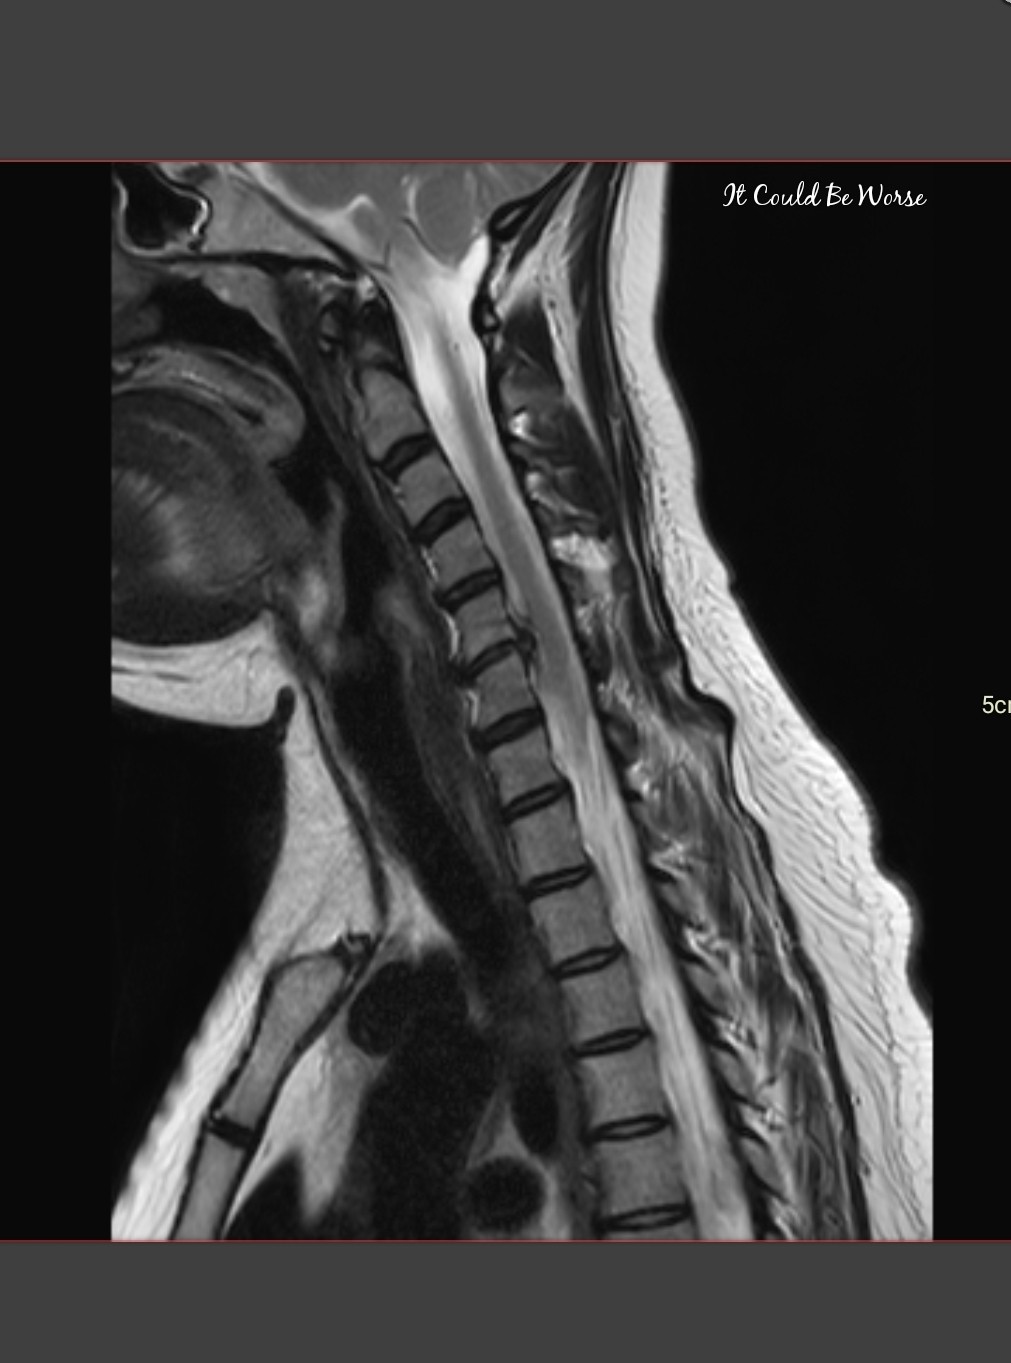

So, I drove back to the VA, and got a CT scan of my neck and spine. I had assumed I would have to wait until the next day to get my report back considering it was late afternoon, but within the hour, my primary care doctor was calling me back and telling me good news, nothing was broken! But bad news, it looks like I have a herniated disc on my C3/C4 spine – which was never there before or after surgery, or in any of the other CT scans I’ve had done – and you know I’ve had plenty. (See image below. This is an older CT scan I had before my ACDF surgery; you can see there is no herniated disc at C-3/C-4.)